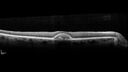

Pattern Dystrophy with Collapsed Vitelliform

74 year old female with vision loss in eye with collapsed vitelliform lesion.